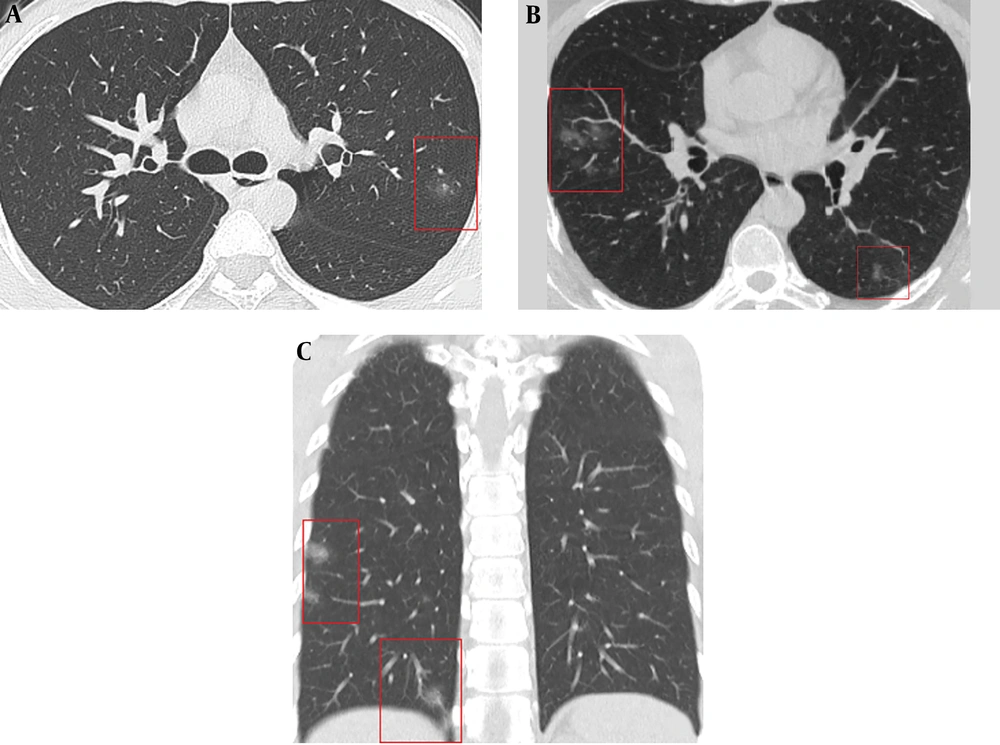

There was an overall agreement regarding main CT pattern classification for intra-observer (K = 0.931, P < 0.001), and inter-observer readings (K = 0.912, P < 0.001). According to the time between symptom onset and initial CT (1 - 11d), three stages of lung CT were assigned: stage-1: 1 - 3d, stage-2: 4 - 7d, and stage-3: 8 - 11d. The imaging findings of each stage of the disease are summarized in Table 2 and Figure 1. At stage-1 (1 - 3 days) the main CT imaging manifestations were (A) single GGO and (B) multiple GGO (Figure 2). When the course of disease progresses 4 - 7 days (Figure 3), the main imaging features were crazy paving GGO mixed with partial consolidation pattern (E). Other imaging features included multiple GGO pattern (B), nodule pattern (C), crazy paving GGO pattern (D) and consolidation pattern (F). When the disease reached 8 - 11 days (Figure 3), the main CT imaging features were consolidation pattern (F), and pattern (E). Two patients underwent CT examination on the first and fourth days of symptom onset, respectively; however, no imaging findings were observed. The total segments of lung involvement in each stage were summarized as 3 (range from 1 to 5), 5 (range from 3 to 7, P < 0.001, compared to that of stage-1), and 6 (range from 3 to 8, P < 0.001, compared to that of stage-1) in each stage.